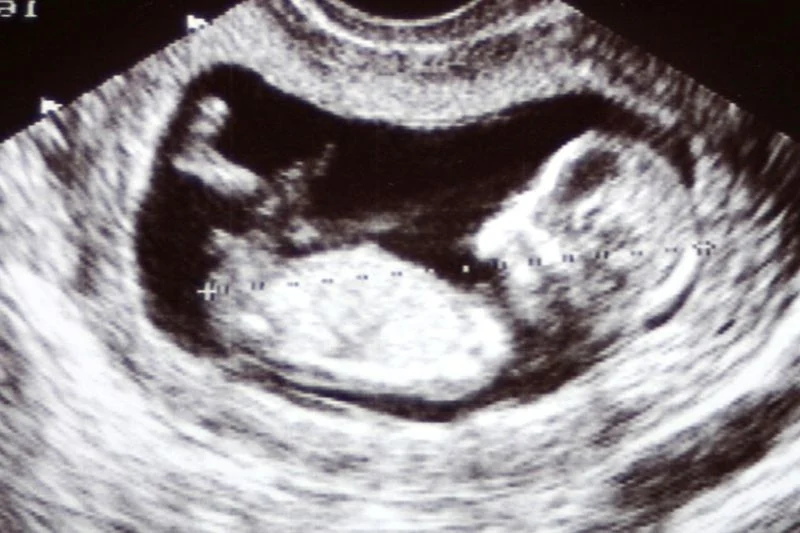

- Den første scanning: Ofte omkring uge 7-9 vil du blive tilbudt en tidlig scanning. Dette er et magisk øjeblik, hvor du for første gang kan se det lille hjerte blinke. Scanningen bruges til at bekræfte, at graviditeten er placeret korrekt i livmoderen, fastslå en mere præcis terminsdato og se, om der er et eller flere fostre.

- Screeninger: Du vil blive tilbudt forskellige screeninger, såsom en nakkefoldsscanning omkring uge 12. Formålet er at vurdere sandsynligheden for visse kromosomafvigelser. Det er vigtigt at huske, at dette er et tilbud. Du bestemmer selv, om du ønsker at tage imod det, og din jordemoder vil guide dig gennem beslutningen.